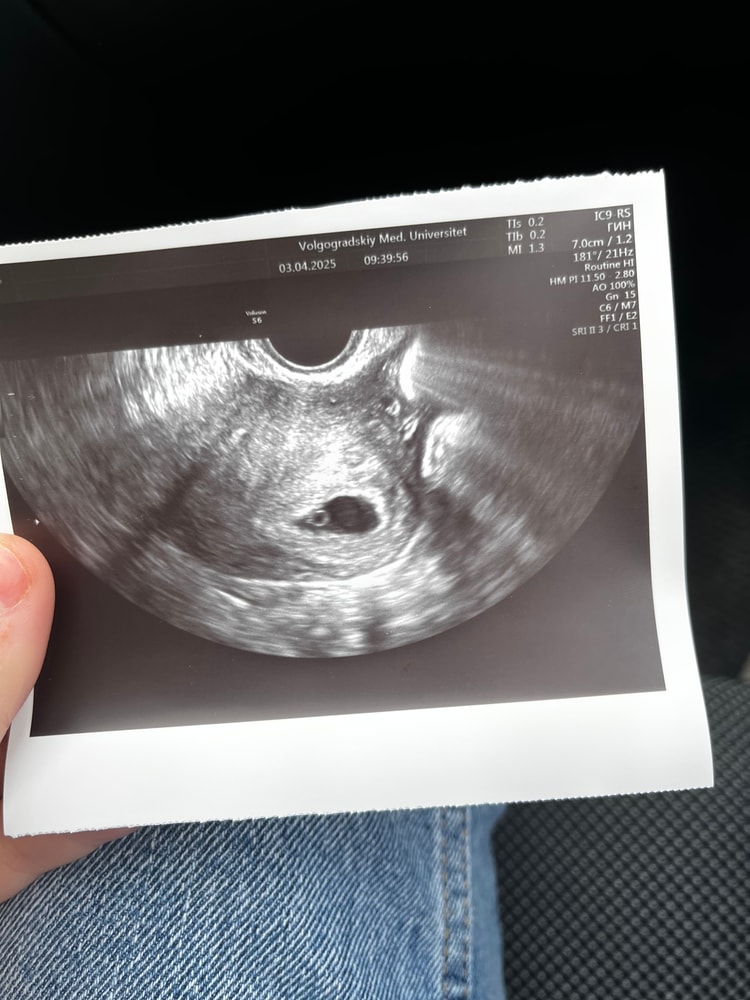

УЗИ 23 дпп

Результаты УЗИДевочки, что скажете по узи ?

Ре особо ниче не смотрела, узи длилось минуту от силы , смущает, что эмбриона нет еще, ну может она не рассматривала, не знаю

сегодня 23 дпп

Желточный мешочек не померили, хотя видно его. Да и эмбрион вроде наклевывается

jillonix, жм померила вроде 2,9 , а по снимку я не разбираюсь есть эмбрион или нет

Александра , цель этого узи - увидеть в матке плодное яйцо. Если его нет, а хгч есть - может быть внематочная, ее как раз на этом сроке исключают. А через две недели смотрят уже сердцебиение. Каждое узи имеет свою цель. А по картинке желточный мешочек видно, размер у него соответствует сроку. Все нормально.